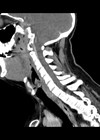

Submandibular haematoma with airway obstruction following a warfarin overdose

Submental and submandibular abscesses are frequent in oral and maxillofacial surgery; on the other hand submandibular haematomas are uncommon. However, we encountered a submandibular haematoma, initially masked as a Ludwig’s angina, which was compromising the airway of a warfarinised patient...